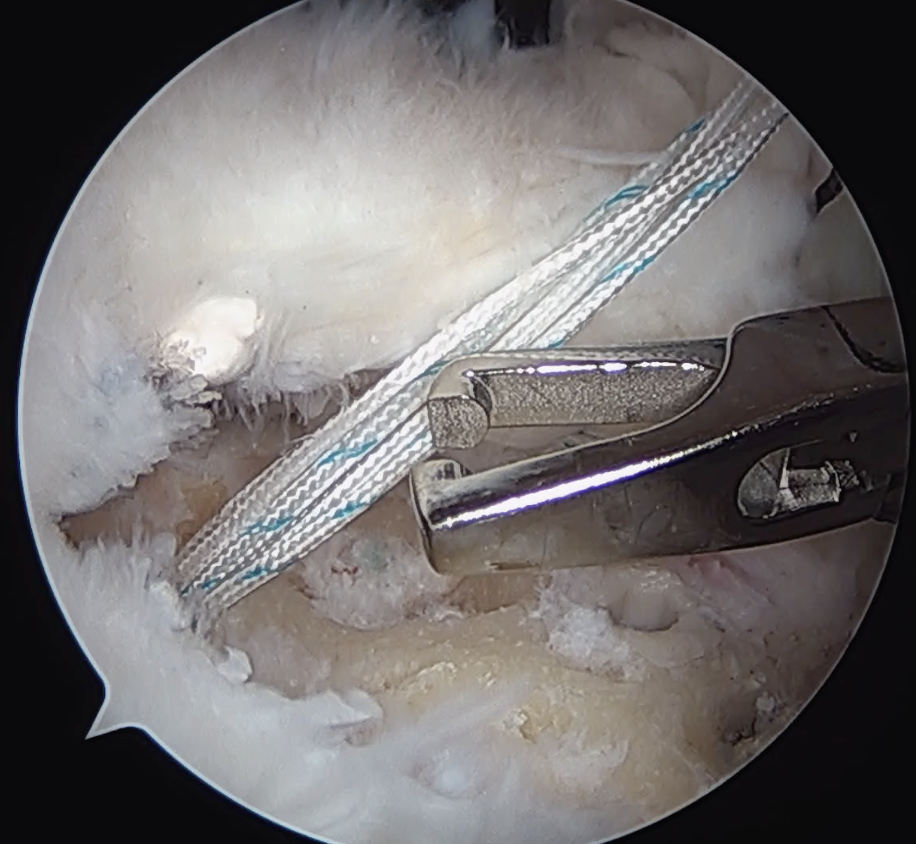

Double row / suture bridge

- use medial row sutures

- secure in knotless lateral row anchors

Trans-osseous equivalent / suture bridge

- cross sutures from medial row to lateral row

- increase contact between cuff and footprint